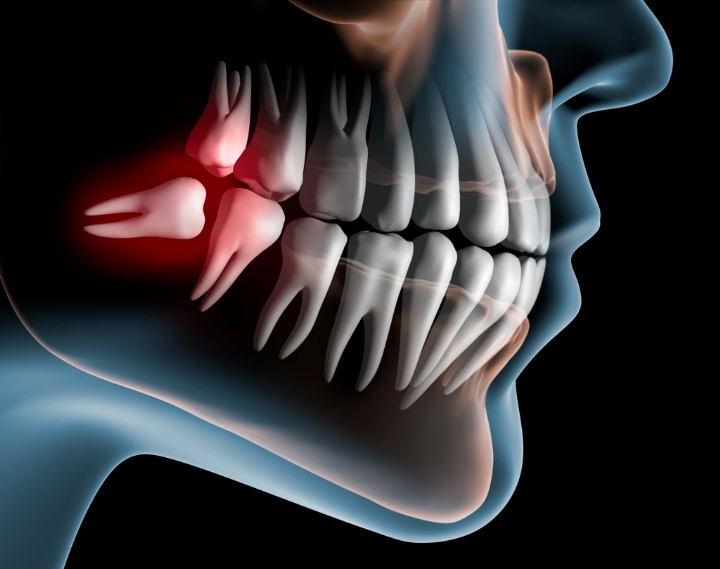

親知らずとは、正式には第三大臼歯(だいさんだいきゅうし)と呼ばれる、人間の永久歯のなかで最も遅く生える奥歯のことを指します。10代後半から20代前半にかけて上下左右の奥歯の一番後ろに1本ずつ生えるのが一般的ですが、なかには1本も生えてこない人もいます。3本しか生えない人や、2本しか生えていない人もいます。

生える本数や生え方に個人差があるのが特徴で、斜めや横向きに生える、歯ぐきの中に埋まったままになるといった方も珍しくなく、トラブルの原因になることもあります。

親知らずがまっすぐ生えていない場合、隣の歯を押して歯並び全体を乱す可能性があります。親知らずはまっすぐ生えることが少なく、斜めや横向きに生える方が非常に多いです。

斜めや横向きに生えると、後ろから歯列を押す力がかかり、一部の歯が歯列から飛び出してしまうことがあるのです。

親知らずが斜めや横向きに生えている場合は、歯ぐきを切開したり、骨を一部削ったりする必要があるため、抜歯の難易度は高くなります。

まず、局部麻酔を使用して感覚を麻痺させてから、歯茎を切開して親知らずを露出させます。歯茎を切開するだけでは親知らずが十分に露出しない場合は、顎の骨を削ることもあります。

親知らずを露出させたら、歯を分割していきます。斜めや横向きに生えている場合は真っ直ぐに引き抜くことができないので、歯をいくつかに分割して少しずつ取り出す必要があるのです。